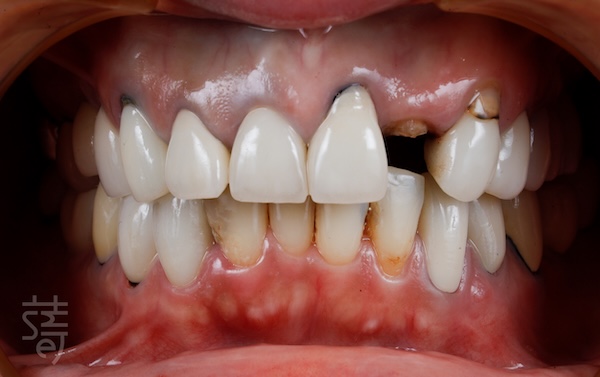

張小姐身為房仲業務,很清楚一個溫暖、親切的笑容,往往能拉近與客戶的距離。這次重建,她也特別重視笑容的整體協調感。

蒔美透過 DSD 數位微笑設計,結合臉部掃描、3D 建模與動態攝影,不只設計牙齒,更納入五官比例、唇形弧度與微笑時的臉部肌肉變化。

在這樣的精細設計下,她的笑容不再只是整齊白牙,而是自然融入整張臉,表情看起來更和諧、有精神,說話時也更自在了。